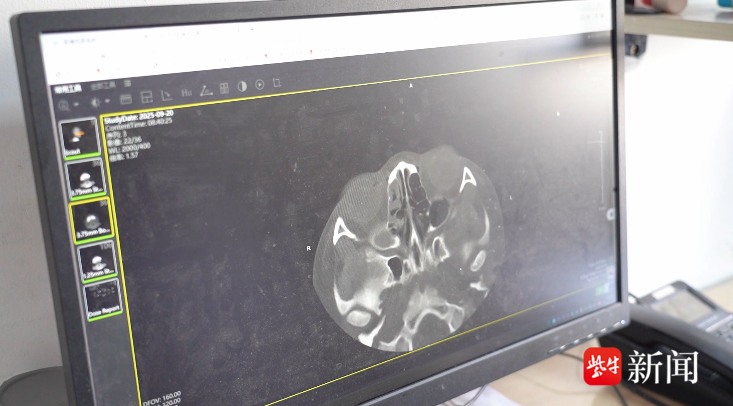

在经过CT检查后,果然发现孩子的鼻腔内有一个异物。“由于异物存留时间过长,已经被鼻子内的肉芽组织包裹,表面上看与普通的鼻甲组织相似,所以才会被误诊。”胡亚娟解释道。